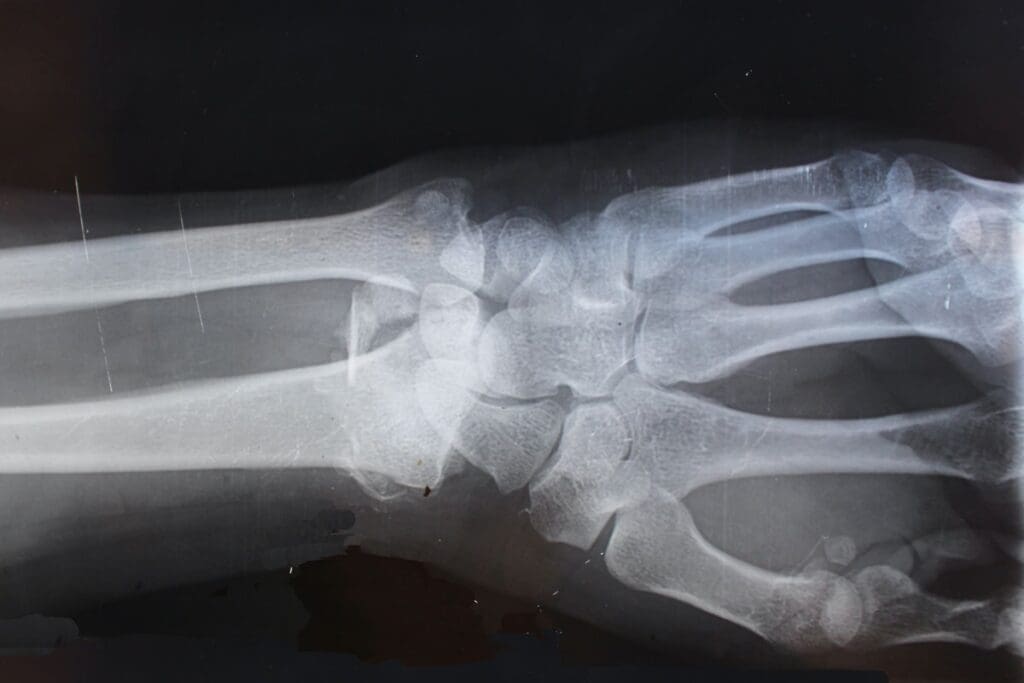

Enchondroma is a benign tumor that starts in cartilage. It’s found in the bones of the hands and feet. These tumors are usually painless but can hurt or even break bones if they grow big.

- Imaging Studies: X-rays, CT scans, MRI scans, and bone scans help find the tumor’s location, size, and how far it has spread.

Doctors use X-rays, CT scans, MRI scans, and bone scans to diagnose bone tumors. A biopsy might also be needed to confirm the diagnosis.